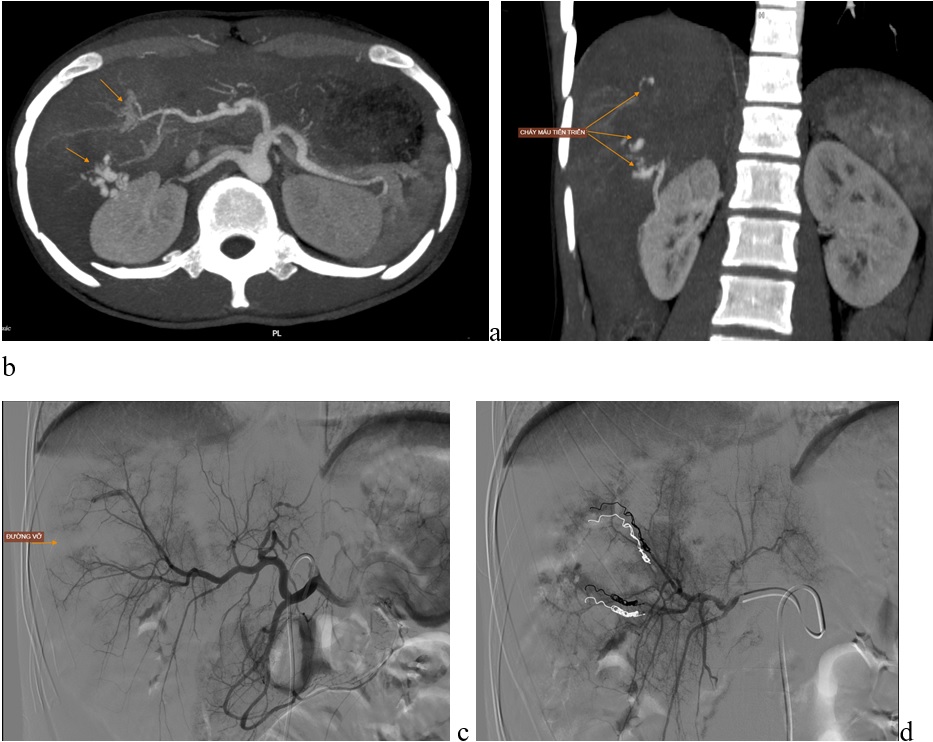

Hình a, b: Cắt lớp vi tính vị trí gan vỡ chảy máu tiến triển

Hình c, d: Chụp mạch DSA xác định mạch tổn thương và coils tắc mạch.

Bệnh nhân nam, 21 tuổi, vỡ gan độ V được điều trị can thiệp cầm máu

Chỉ trong thời gian ngắn từ 30 phút – 60 phút thực hiện thủ thuật, dưới sự hướng dẫn của máy DSA, kíp bác sỹ thực hiện kỹ thuật Điện quang can thiệp đã đưa các ống thông nhỏ qua lỗ kim chọc từ động mạch đùi (khoảng 2mm), dùng các vật liệu phù hợp để gây tắc mạch máu tổn thương, chấm dứt tình trạng chảy máu, người bệnh sẽ tiếp tục được điều trị hồi sức hỗ trợ. Cả bốn bệnh nhân hiện tại đã ổn định, các tạng tổn thương được điều trị bảo tồn không phẫu thuật.